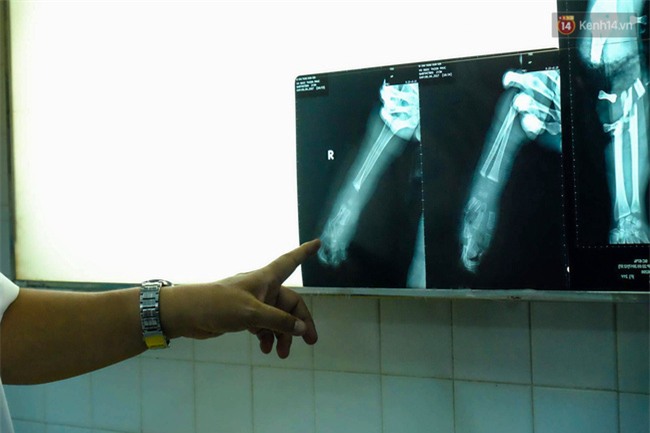

Hình ảnh chụp lại từ cho thấy cổ tay bé trai bị gãy.

Theo bác sĩ Tường, quá trình điều trị cho thấy bé P. bị thương ở cả mặt trước và mặt sau của tay với tỉ lệ lên đến 75%.

"Vì bị thang máy đè nên nhiều ngón tay của bệnh nhi bị tím tái. Khả năng tay của bé có thể bị hỏng rất cao do các mô bị dập nát chứ không đứt ngang như những trường hợp thông thường. Sau khi tiếp nhận, chúng tôi đã cố gắng nối các gân, cơ cho đứa bé", bác sĩ Tường nói.